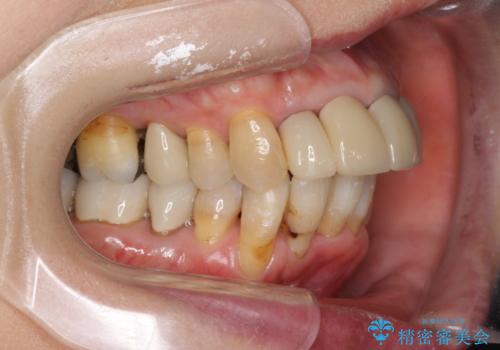

矯正を含む全顎治療

- 前歯の見た目・歯並び・銀歯の見た目の改善を求めて来院されました。

まずガタ付きの強い歯並びをマウスピース矯正インビザラインで整えたのち、セラミック治療による審美性の改善を計画します。

矯正治療が終わったのちに、精度の高いセラミックを装着することでより安定した噛み合わせとなり審美性も兼ね備えた口腔内状態で治療を終了し、今後のメンテナンスを行っていくことができます。